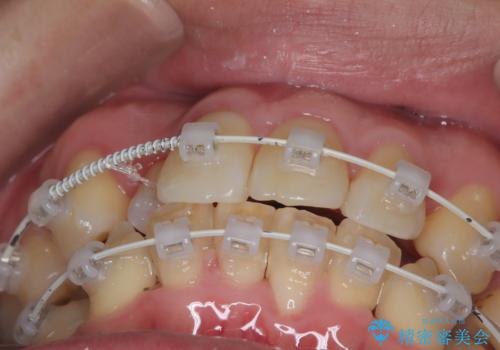

- 矯正装置

- ワイヤー(審美装置)

- 「歯のデコボコと前歯が引っ込んでいるのを治したい」を主訴に来院された患者様です。

デコボコの量が多かったため上下左右4を抜歯してワイヤー矯正で治療を行いました。

正面から見たときに右上2が全く見えないくらい、右上2が後ろに引っ込んでいる状態でしたが綺麗に並べる事が出来ました。